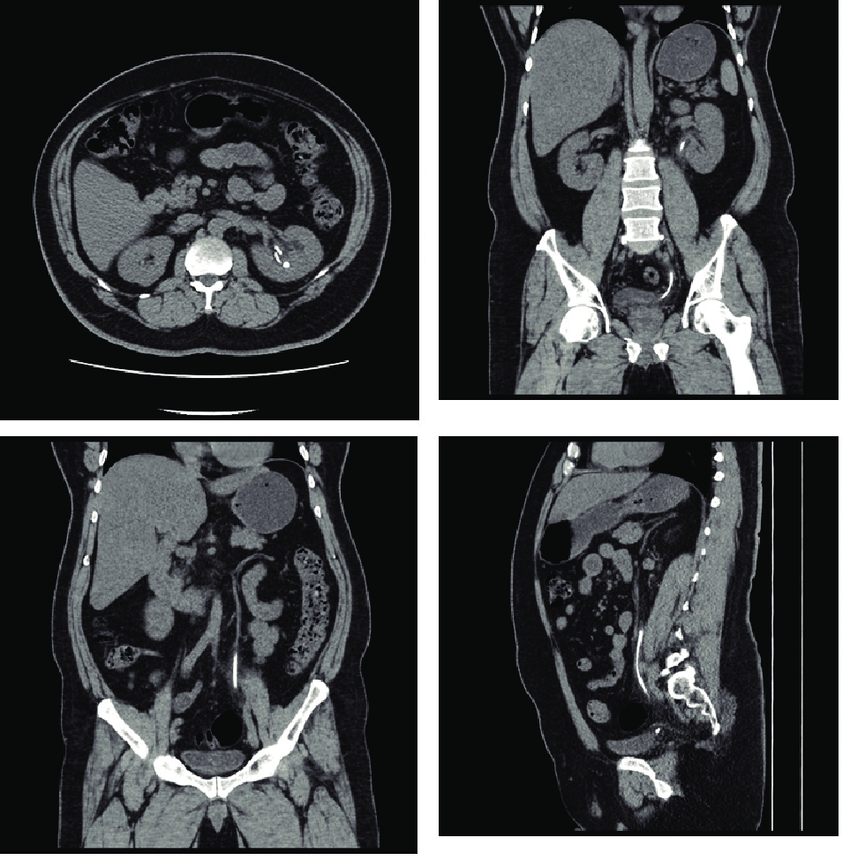

Overview of CT KUB Scan

CT KUB (Kidneys, Ureters, and Bladder) scan is a non-invasive imaging technique that utilizes computed tomography (CT) to provide detailed cross-sectional images of the urinary tract. This painless and efficient procedure involves the use of X-rays and computer processing to generate a three-dimensional representation of the kidneys, ureters, and bladder, offering valuable insights into their structure and function.

CT KUB is commonly used to diagnose and evaluate various conditions affecting the urinary tract, including kidney stones, tumors, infections, and obstructions. It can also assess the size and shape of these organs, detect abnormalities, and monitor the progress of treatment for existing conditions. The procedure is relatively quick and requires minimal preparation, making it a preferred option for many patients and healthcare providers seeking a comprehensive assessment of the urinary system.